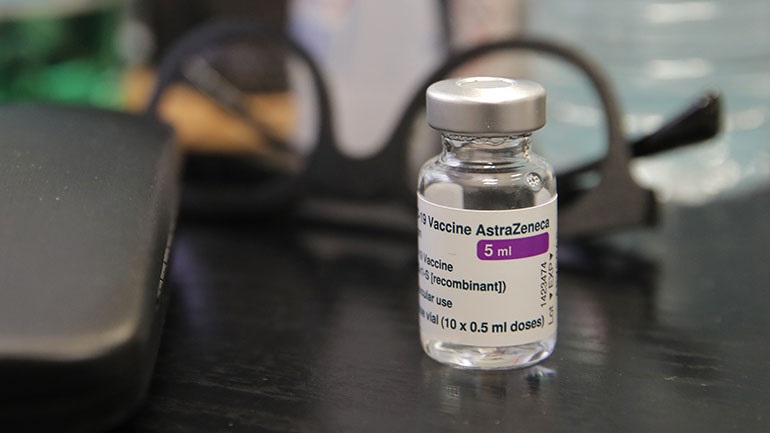

Η απάντηση της AstraZeneca για τον κίνδυνο εμφάνισης θρομβώσεων μετά το εμβόλιο

Η AstraZeneca Plc ανακοίνωσε σήμερα ότι πραγματοποίησε έλεγχο σε ανθρώπους που έχουν εμβολιαστεί με το εμβόλιό της κατά του Covid-19, ο οποίος έδειξε ότι δεν υπάρχουν....